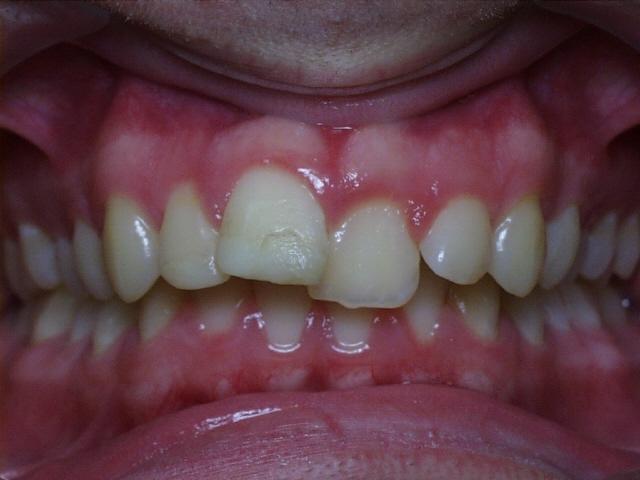

Severe overbite with mild upper and lower crowding.  Treatment time was 29 months.  No permanent teeth were extracted in this case.  The molars were class 2 (upper molars too far forward at start of treatment).  This patient can have bonding performed by his general dentist to repair the chipped front tooth.

Before  ttao1.jpg (30309 bytes)     ttao3.jpg (28155 bytes)  After